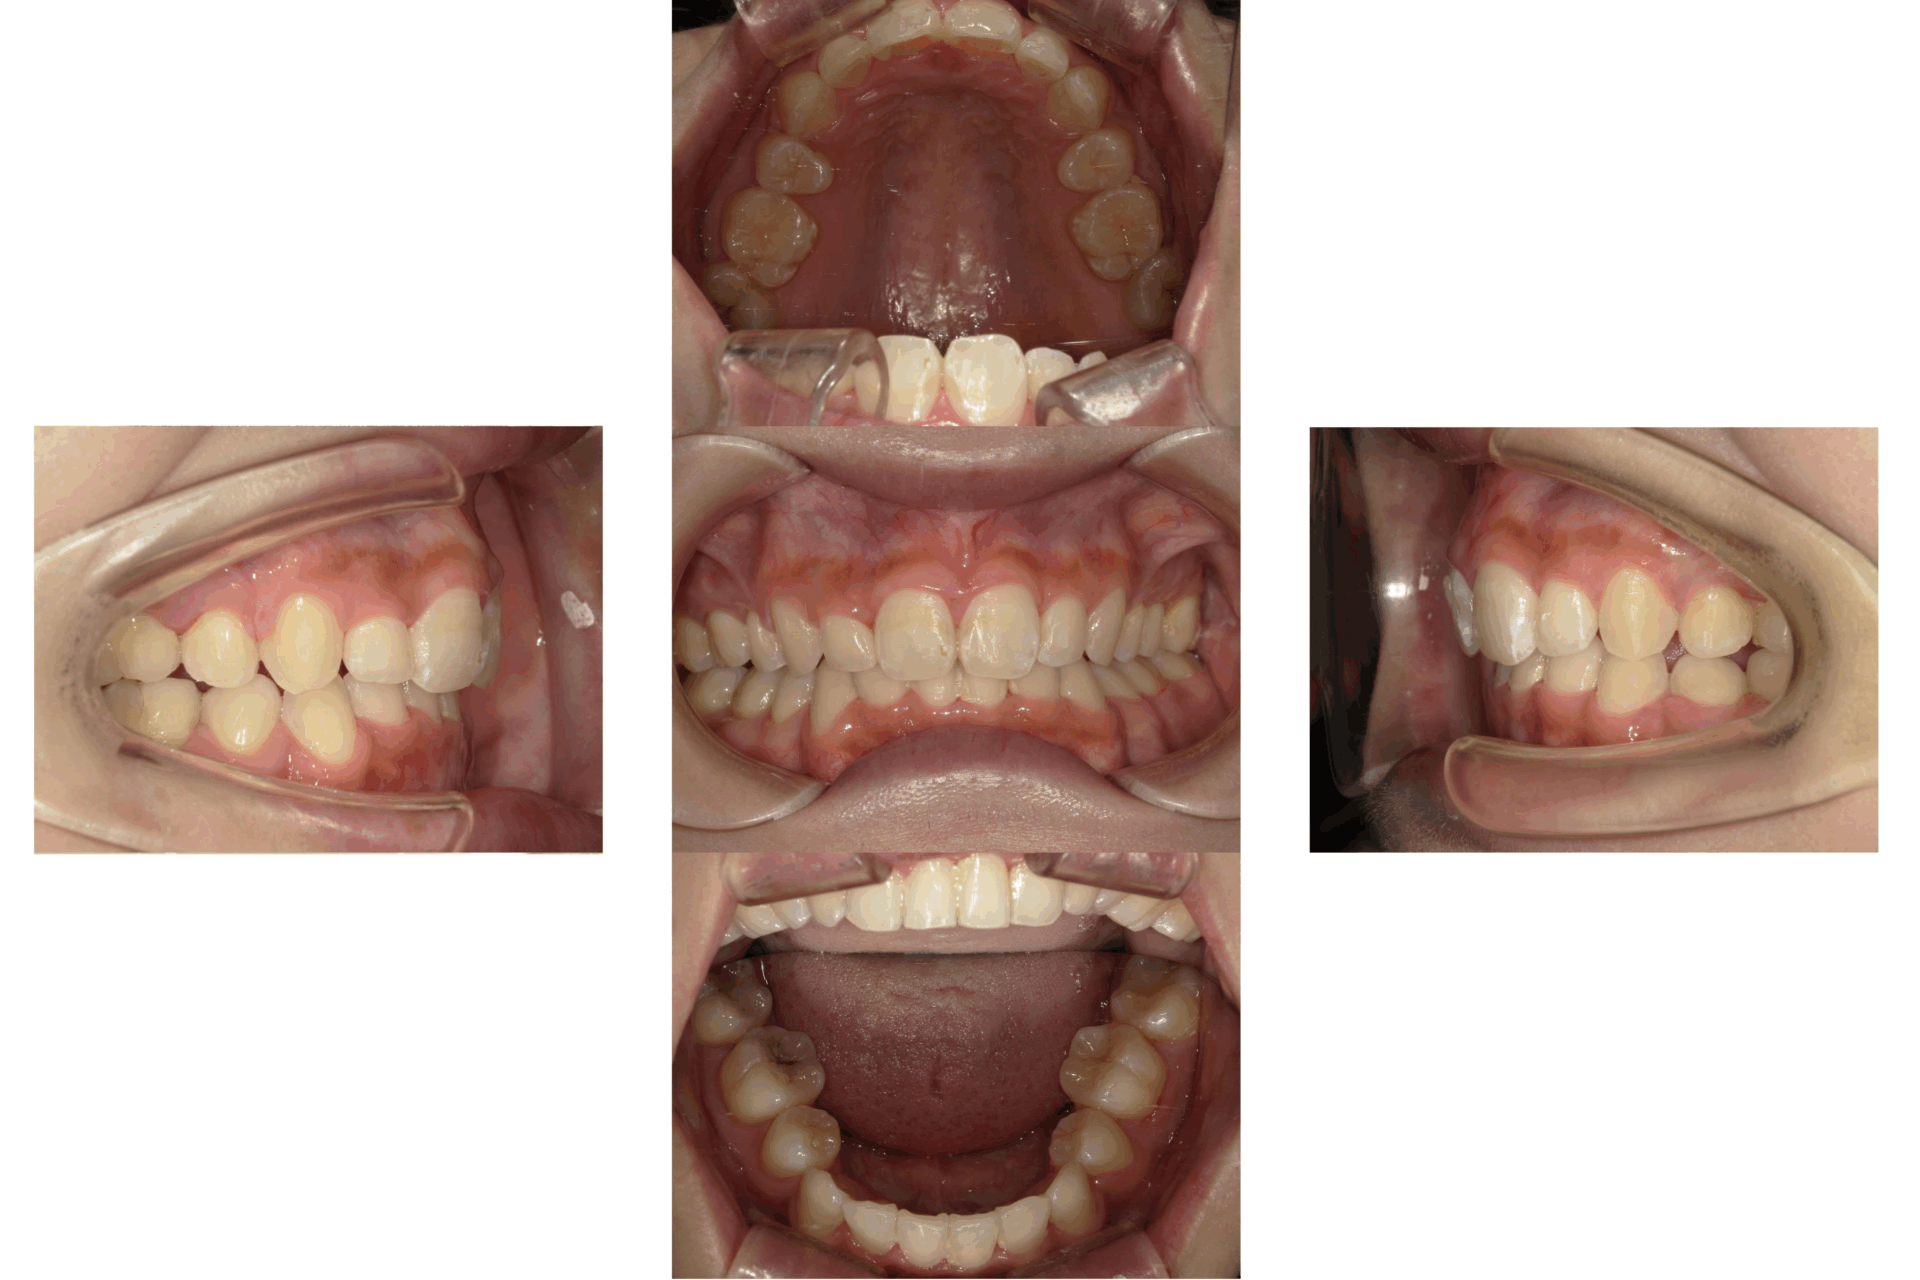

20代、女性、ワイヤー

| 施術内容 | 主訴:全体的に凸凹が気になる 詳細:ワイヤー矯正での歯並び改善 ずっと磨きにくく、臭いが気になっていましたが、 矯正後は磨きやすくなり、臭いも無くなって満足された症例です。 |

| 治療期間 | 16ヶ月(3/13現在 治療終了) |

| 費用 | ワイヤー矯正 60万円(税込660,000円) |